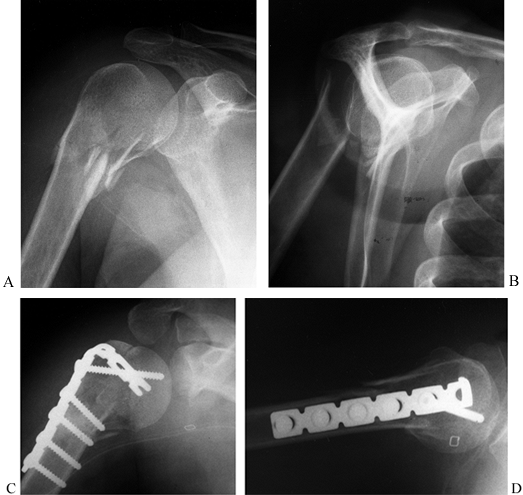

several different fracture patterns depending on the position of the

and internal fixation (47,51) (Fig. 15.10).

![]() |

|

Figure 15.10. A: Anteroposterior radiograph illustrating a comminuted type II glenoid fossa fracture. B: Lateral radiograph of fracture. C: Postoperative AP radiograph illustrating interfragmentary lag screws utilizing the coracoid process for good screw purchase. D: Postoperative lateral radiograph.